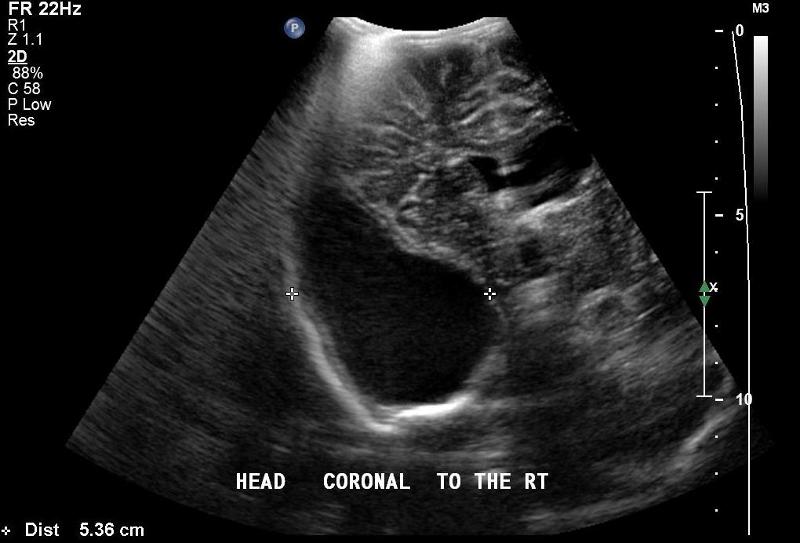

In what is the orientation of a coronal view image of a neonate head scan?

top - superior - superficial

bottom - inferior - deep

right - left

left - right

Explain the coronal view image of a neonate head scan.

slowly angle through the coronal plane

beginning rostrally at the frontal lobes angle posteriorly